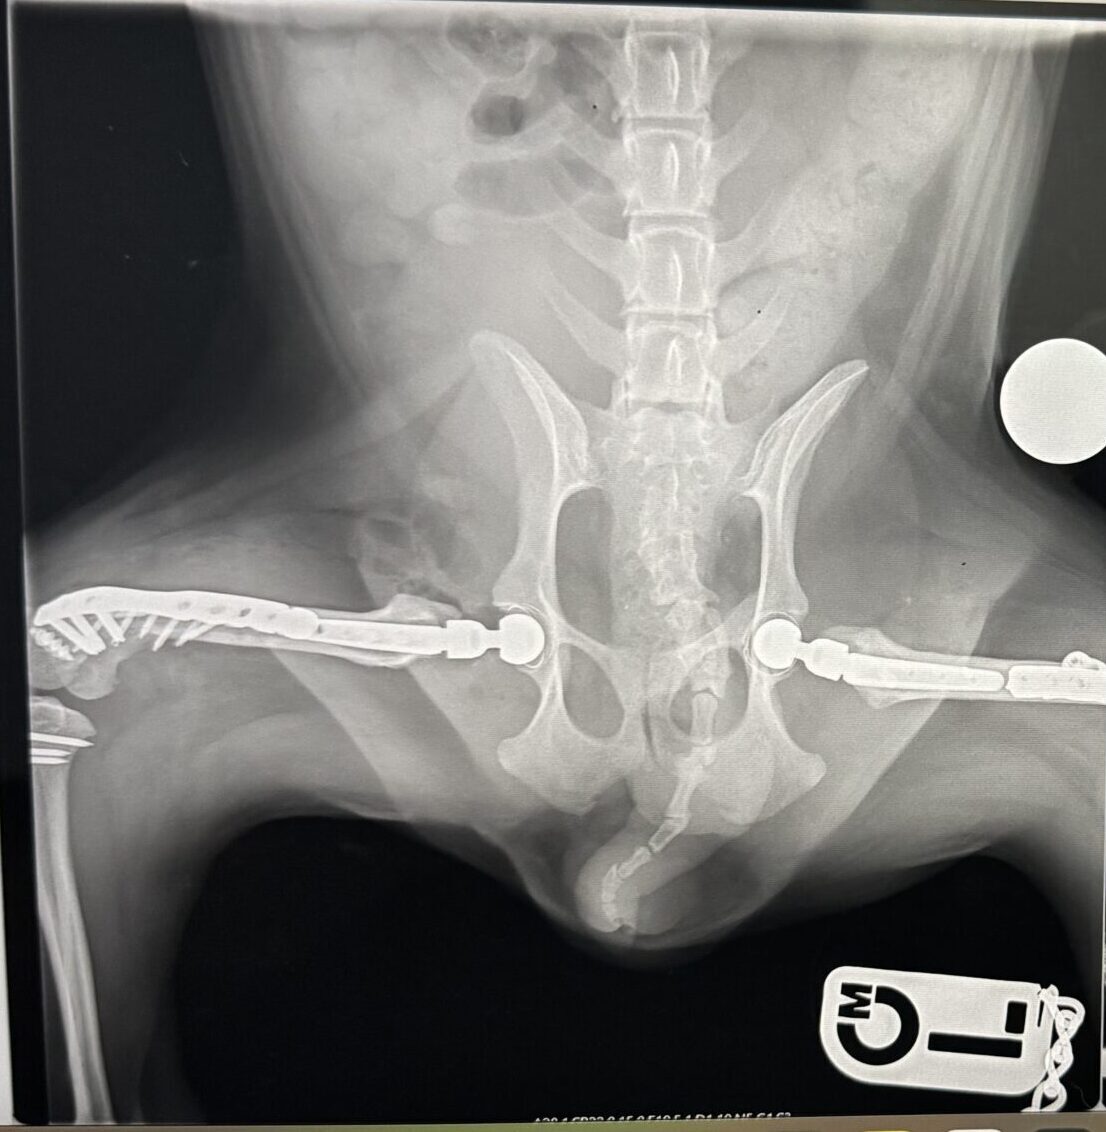

2025年7月7日

両足の手術後の経過観察としてレントゲン撮影を実施しました。

これまで「手術はギリギリ回避できた」と診断されていた右側の股関節に、明らかな痛みとレントゲン上での骨の接触が確認されました。

実際、レントゲンで見える以上に触診でぽにょは痛がっており、歩き方もどこか不自然でした。

すでに両足の手術を終えている影響で、後ろ足を軽くかばうように歩く姿が見られ、右側の太ももの筋肉が明らかに細くなってきていました。

これは術後の経過とも見えていましたが、「痛みで足をしっかりつけない状態」だと診断され、手術適応となってしまいました。

2025年7月18日

手術内容

・右股関節形成不全(根治目的)

・股関節全置換術(右側)

【術中所見】

股関節の円靭帯が断裂していたことが判明。痛みの主な原因はここにあったとみられます。

ぽにょの足にはたくさんの金属がはいっています。

人間でもここまでやるのは大大手術。